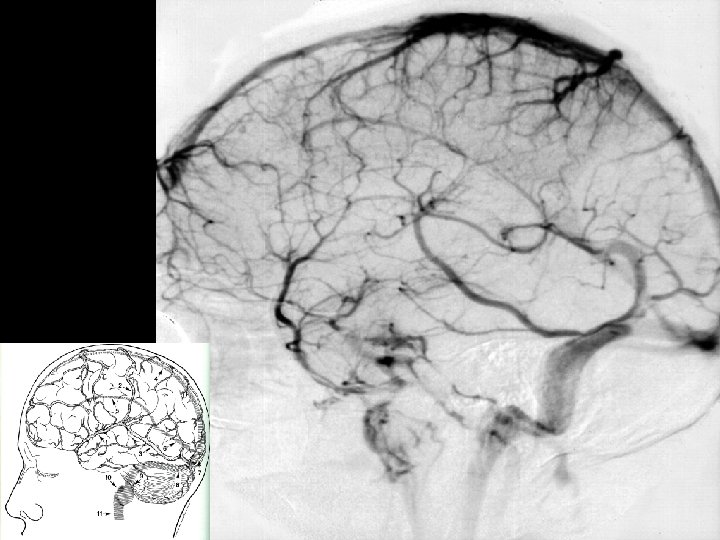

Angiographic digression to aid the understanding of venous angiography Michigan Neurosurgery

Deep Veins Thalamostriate vein Internal Cerebral vein (2) Vein of Galen Septal vein Basal vein of Rosenthal (2) Occipital vein (2) Posterior Pericallosal vein (2) Mesencephalic vein (2) Precentral Cerebellar vein (1) Inferior Sagittal Sinus Straight Sinus Michigan Neurosurgery

Deep Veins Michigan Neurosurgery